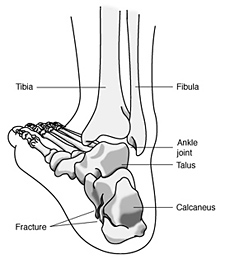

Calcaneal Fracture Broken Heel Bone Plantar Fasciitis Orthopedic Foot and Ankle Specialist Vail Colorado Eagle Vail Mountain Range Community best sale, Calcaneus Fracture Broken Heel Bone Orthopaedic Trauma Association OTA best sale, Calcaneus Fracture Broken Heel Bone Orthopaedic Trauma Association OTA best sale, Calcaneal Fracture Treatment Exercises FAQs Case best sale, Calcaneus Fracture Broken Heel Bone Orthopaedic Trauma Association OTA best sale, Did I Bruise Or Fracture My Heel The Orthopaedic Foot Ankle Center best sale, Causes and Treatment of Heel Pain Dr. John Chrabuszcz OrthoGeorgia best sale, Calcaneus Heel Bone Fractures OrthoInfo AAOS best sale, Did I Break My Heel Bone Dr. Elton best sale, Calcaneal fracture Wikipedia best sale, Calcaneus Fracture Broken Heel Bone Orthopaedic Trauma Association OTA best sale, Calcaneus Heel Bone Fractures OrthoInfo AAOS best sale, When There Is A Traumatic Fracture Of The Inferior Heel Spur best sale, Calcaneus Fracture Broken Heel Bone Orthopaedic Trauma Association OTA best sale, Bilateral broken calcaneal spurs BMJ Case Reports best sale, Stress Fracture of the Calcaneus Everything You Need To Know Dr. Nabil Ebraheim best sale, Dealing With a Fractured Heel Bone best sale, Calcaneus Fracture Surgery Heel Surgery Procedure Recovery best sale, Plantar Fasciitis vs. Stress Fractures Heel That Pain best sale, Calcaneus Fracture Broken Heel Bone Orthopaedic Trauma Association OTA best sale, Pain In heel after Fracture Calcaneum Fracture best sale, When There Is A Traumatic Fracture Of The Inferior Heel Spur best sale, Can a Stress Fracture Cause Heel Pain The Foot Care Group Podiatrists best sale, Fracture of the Heel Bone Calcaneus Central Coast Orthopedic Medical Group best sale, Calcaneal Fracture Symptoms Causes Treatment and Rehabilitation best sale, Calcaneal Fractures Physiopedia best sale, When There Is A Traumatic Fracture Of The Inferior Heel Spur best sale, Fractures of the Heel UConn Musculoskeletal Institute best sale, Fractures Breaks and Plantar Fasciitis Heel That Pain best sale, Calcaneal Fractures Physiopedia best sale, Calcaneus Fracture Broken Heel Bone Orthopaedic Trauma Association OTA best sale, Plantar Fasciitis vs Stress Fracture Angleton Emergency Room Open 24 HRS best sale, Causes of Heel Pain Why does my foot hurt Bone Talks best sale, Heel Stress Fracture Heel Pain Treatment Melbourne Podiatrist best sale, Plantar Fasciitis and Bone Spurs OrthoInfo AAOS best sale.